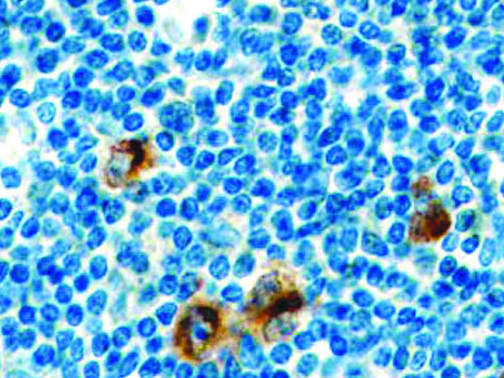

It is the ICU physician who is most likely to witness one of the deadliest manifestations of the abnormal immunological response, the cytokine storm syndrome (CSS). This response is also referred to by some as the cytokine release syndrome (CRS). CSS is characterized by continuous activation and expansion of macrophage and lymphocyte populations, which secrete large amounts of cytokines, causing the cytokine storm. This massive cytokine release is akin to hemophagocytic lymphohistiocytosis (HLH) disease, a syndrome characterized by initial unchecked and persistent activation of cytotoxic T lymphocytes and NK cells.

Clinical and laboratory manifestations of HLH include fever, enlarged liver and/or spleen, neurologic dysfunction, coagulopathy, liver dysfunction, cytopenias (i.e., low levels of erythrocytes, leukocytes, and/or platelets), hypertriglyceridemia, hyperferritinemia, hemophagocytosis, and eventually diminished NK cell activity as the immune system becomes progressively paralyzed. HLH can be familial (primary HLH) or secondary to another disease process (sHLH), such as rheumatic disease, in which it is referred to as macrophage activation syndrome (MAS, characterized by elevated ferritin).